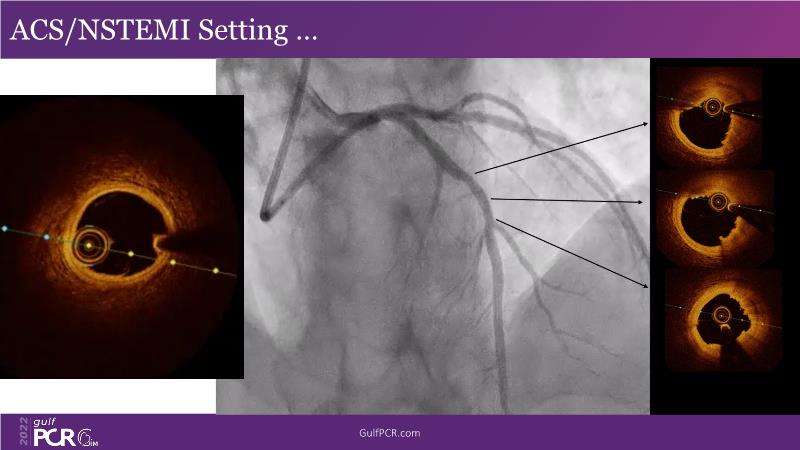

In this session, follow a LIVE case from the Chest Diseases Hospital in Kuwait and learn what the best strategy is to treat patients who present with a very long calcified coronary artery lesion, as well as how to select the best device and which different types of stents can be used.

- To learn correct interpretation of a long-calcified lesion and how to adopt procedural strategy

- To understand value of intracoronary imaging in patient treatment